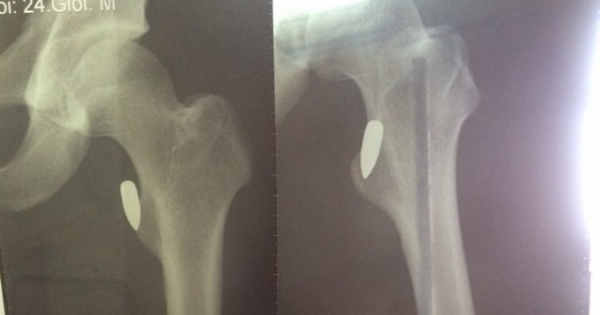

VĐV Pencaksilat  bị trúng đạn khi đang đi trên đường

Đang đi xe máy trên đường, anh Lộc nghe thấy tiếng nổ và dừng xe lại thì thấy máu đã chảy lênh láng ở đùi.